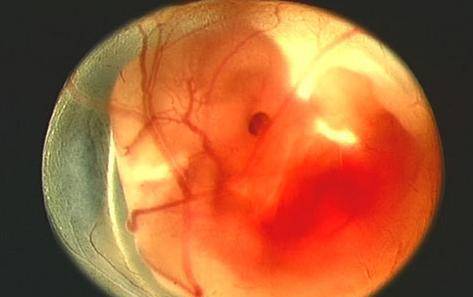

怀孕一个月,胎儿的发育

在这个时候,胎儿正在开发他最终的面部和颈部的结构。胎儿心脏和血管继续发展。肺,胃和肝开始发育。如果你进行妊娠试验,会显示阳性。

怀孕两个月,胎儿的发育

宝宝现在的体积略大于1.27厘米。眼睑和耳朵正在形成,你可以看到鼻尖。手臂和腿部形成良好。手指和脚趾长得更长,更清晰。